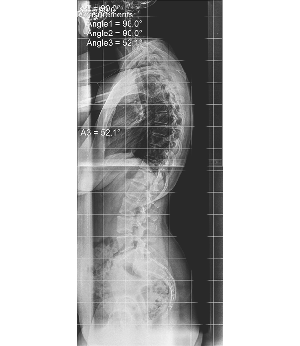

Έφηβη με Σκολίωση αριστερή θωρακοοσφυϊκή 27,4°, μεγάλη απόκλιση λεκάνης δεξιά και μεγάλη αισθητική παραμόρφωση.

Και κύφωση τ. Scheuermann 52°. Στην ασθενή εφαρμόσθηκε κηδεμόνας Κυφοσκολίωσης SPONDYLOS και άρχισε να κάνει ασκήσεις για σκολίωση και κύφωση Schroth και SEAS. Ένα έτος μετά η διόρθωση στην κλινική της εικόνα ήταν εντυπωσιακή. Η σκολίωση της είχε μειωθεί στις 16° και η συμμετρία της ήταν άψογη, ενώ η κύφωση της ήταν στα απόλυτα φυσιολογικά 33°.